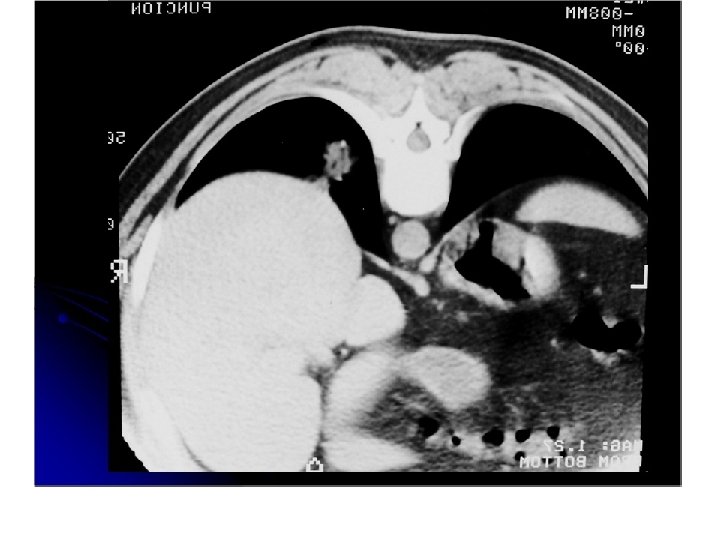

Tumor de células grandes, periférico, lobulado, con neumonitis post obstructiva. Adenomegalias ipsilaterales.

Carinoma dde celulas grandes • Se denominan asió por exclusión • generalemte son periféricos y grandes